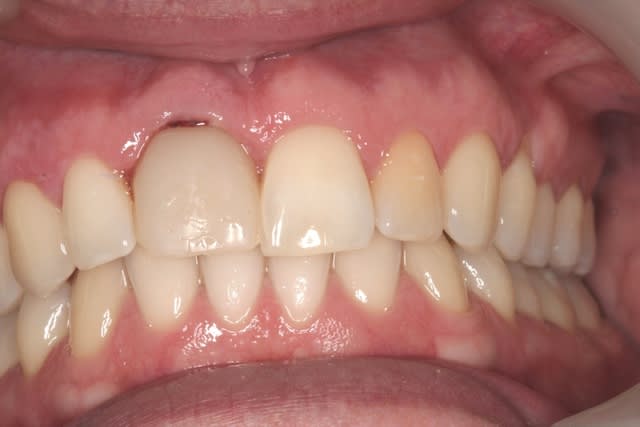

çà manque un peu de cas en ce moment...alors en voilà un ptit au passage...

11 avec résorption interne

EII avec MCI sur du dentium (4.5/14) comblement du gap vestibulaire avec du kasios tcp (très constant dans les résultats...et très économique)

pas de photos de chir par contre...j'ai du les effacer par erreur...grrrr...

la prothèse d'usage a été réalisée par ma petite associée...mais j'étais là pour superviser et faire quelques photos...;-)